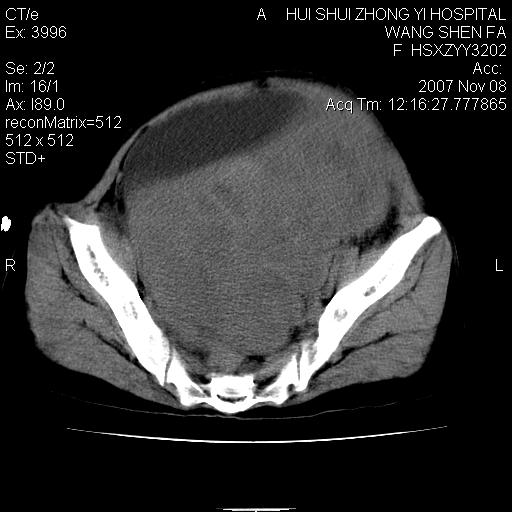

标题: CT10389:女,38岁,腹部巨大包块 [打印本页]

标题: CT10389:女,38岁,腹部巨大包块

腹部巨大包块半年,质硬,边界不清。

下腹部巨大软组织影,密度不均匀,并可见分隔,病灶边缘较清,肠管受压移位。子宫未显示。盆腔、双侧腹股沟未见明显肿大淋巴结。考虑:1.卵巢病变可能性大,囊腺癌>卵巢癌>囊腺瘤.2.多发性阔韧带子宫肌瘤待除外.

腹腔及盆腔内可见巨大软组织肿物影,内部密度欠均匀,边界尚清晰,周围组织受压移位明显,膀胱前上移位,右侧输尿管受压明显,上端扩张肾盂轻度积水。考虑:1卵巢病变可能性大,囊腺癌>卵巢癌>囊腺瘤.2 子宫病变,子宫肌瘤?

盆腔及下腹部多发肿块,密度不均,与子宫关系密切,周围肠管受压改变,盆腔内未见肿大淋巴结,考虑多发性巨大子宫肌瘤可能。直接手术吧!

膀胱向前明显的推压移位,子宫增大明显,肠管推压移位,未见明显的侵润;患者女性,育龄期,考虑多发子宫肌瘤可能性大